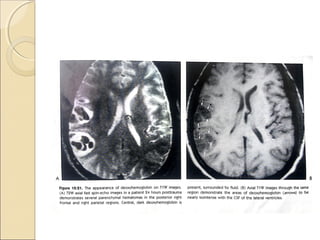

Confusing…evolution of hematomaConfusing…evolution of hematoma

Hyper acute(mts…hrs):oxyHb…O2

binds to 6th

location on iron in heme of Hb

O2…strong ligand, significantly split energy

level of iron….in low spin state…not

paramagnetic

O2Hb blood will have long T1…dark on T1W

image

Any T1 shortening occurs due to water binding

transiently to hydration layer of

protein..shortening T1…iso intense

Due to free flowing without paramagnetic

Acute phase deoxyHb(hrs….days):

Fe in deoxyHb is in ferrous state….no

O2 present

High spin state, paramagnetic because of

presence of 4 unpaired electron….should

cause shortening of T2 with brightness on

T1W.

When O2 falls of Hb , iron molecule

retract slightly inside the porphyrin

ring…allosteric shift of HB

Iron is pulled out of plane of porphyrin,

water is excluded from sensing the

paramagnetic effects of iron.

For significant paramagnetic effect water

must transiently bind to iron…

On T1W deoxy Hb …isointense with

water.

Immobilization of fibrin,Hb, paramagnetic

iron molecule with in semisolid

gelatinaous clot reduces the mobility of

these substances….disturbing local

magnetic field

Rapid dephasing and loss of signal inT2W